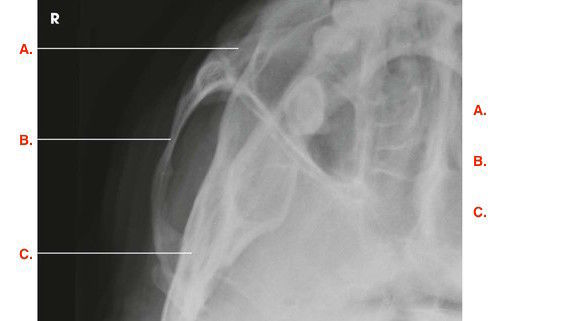

Question

Label the image

998f0cc7-60fb-4e21-9b54-73af4807c345 (image/jpeg)

Answer

temporal process of zygomatic bone

zygomatic arch

temporal bone